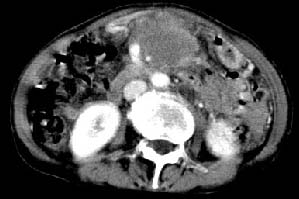

胰腺受压前移,胰管扩张,应为腹膜后占位,病灶密度不均,有低密度坏死区,强化扫描强化不明显腹腔干动脉受侵,考虑腹膜后恶性占位

从发病部位(腹主动脉周围)及增强方式(均匀轻度强化、少量坏死)和病变形态(较大、多结节形)符合腹膜后淋巴瘤,建议颈部病变活检。

我的第1诊断还是考虑是淋巴类病变1}。从病灶形态上看不是很规则,但其更向是多个结节的融和,其内有少许坏死,整个病灶的强化不是很明显,临近左恻肠间隔有增厚,2}我认为更重要的一点的是肠系膜有明显增厚呈片状。3}患者的脾脏不大其未见异常病灶。结合以上几点我首先考虑是转移性{但对此诊断我觉得不足之处;转移性的淋巴结肿大融合为什么没有坏死?}。{另外患者无大便习惯改变及血便,其发现右颈包块在今年过年无意发现}。以上是我的浅分析望各位战友继续讨论!谢谢!!

主动脉-胰腺间隙可见巨大分叶状软组织肿块影,包绕腹主动脉、腹腔干及其分支、腔静脉等大血管,增强呈无明显强化,临近脏器明显受压移位,增强示有分界。肝右叶可见局限性低密影,边缘清楚。

考虑腹膜后淋巴瘤。

影象表现:平扫,首先可见胃壁明显增厚,内外边缘清晰,外缘光滑,内边缘不归整,同时胃腔明显缩小。

再看从肠系膜根部到胰腺后主动脉及上腔静脉周围可见相连的较大的软组织肿块影,形态不规则,呈明显

的大小不等的分叶状,其中密度较均匀但其中可见条状低密度区,肿块边缘比较清晰周围的小肠受压移位

明显且堆积。

增强所见,腹腔动脉,肠系膜上动静脉被肿块包绕,结合平扫的条状低密度区恰好位于血管周围,较大的

肿块强化不明显(遗憾的是没有标上ct值)但胃壁强化的十分明显。